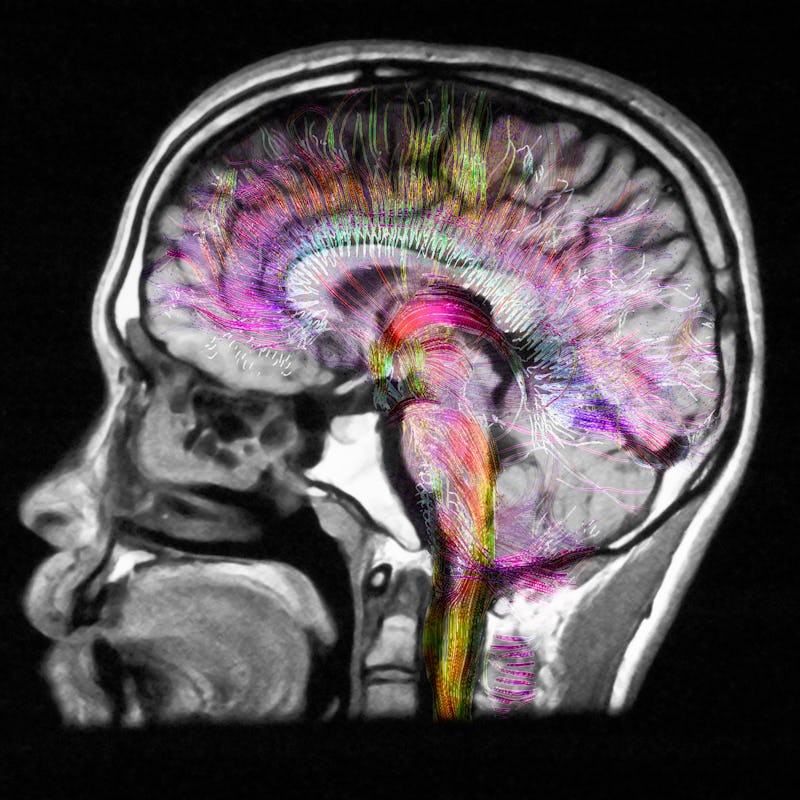

The crux of Ozempic is that it seems to dull the activity in the hunger centers of the brain, which in turn makes you eat less and experience fewer cravings. But one of the challenges of neuroscience is that while we know a lot about the brain, there’s a lot more we don’t know. This extends to the neuroscience of obesity and the circuits involved in controlling hunger and eating behaviors. Inverse spoke to several experts studying Ozempic and drugs like it to try and understand how much we know, and don’t know, about how these drugs influence our brain’s delicate chemistry.

Typically after you eat a meal, cells in the intestine release GLP-1 and the signal travels up to the brain to bind to specific receptors located in an area called the hypothalamus, particularly the arcuate nucleus involved in regulating hunger and satiety signals, Priya Jaisinghani, an endocrinologist and obesity medicine specialist at New York University Langone Medical Center, tells Inverse.

In the arcuate nucleus, two neurons — the cocaine- and amphetamine-regulated transcript (or CART) and proopiomelanocortin (POMC) — pump up their activity, helping you feel full. Other neurons that make a protein called neuropeptide Y are told to stand down, decreasing feelings of hunger.

The other two are the hedonistic pathway associated with reward and pleasure aspects of eating — like craving ramen in the middle of the night — and the cognitive or executive pathway that involves higher-order brain regions like the prefrontal cortex.

Not to mention, neurons like CART neurons aren’t only located in the arcuate nucleus of the hypothalamus. Among many places, they dot the nucleus accumbens, a small structure located deep within the brain in the basal ganglia. It's part of a larger brain system known as the reward pathway or the mesolimbic pathway that’s been associated with addiction and drug abuse. Curiously, this tracks with another of the anecdotal side effects users report is that their desire to drink alcohol disappears with Ozempic, although that is not well studied.